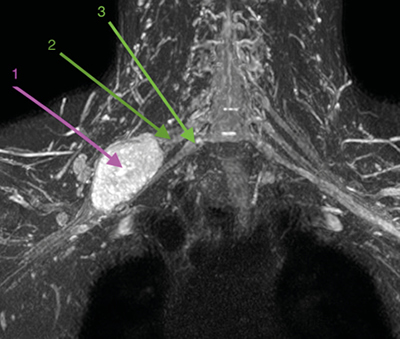

Figura 1